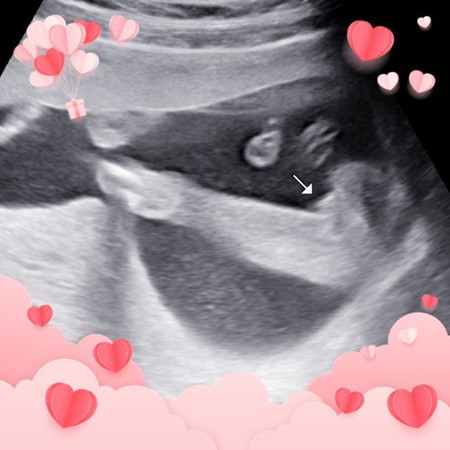

18วีค5วัน หมอบอกว่าหนูเป็นผู้หญิงค่ะ น้องอ้าให้ดูไม่อยากให้แม่ลุ้น แถมชูนิ้วให้แม่ด้วย ดิ้นเก่งมากค่าา🤣